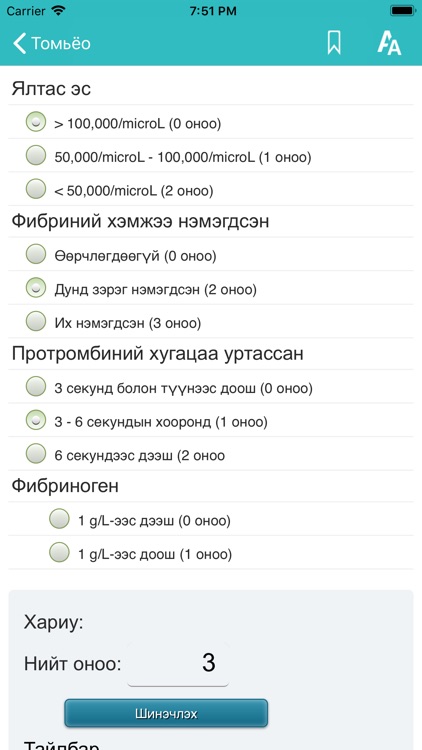

Эрүүл мэндийн лавлах аппликейшн

Эрүүл мэндийн лавлах аппликейшн.

Эрүүл мэндийн лавлах аппликейшн.